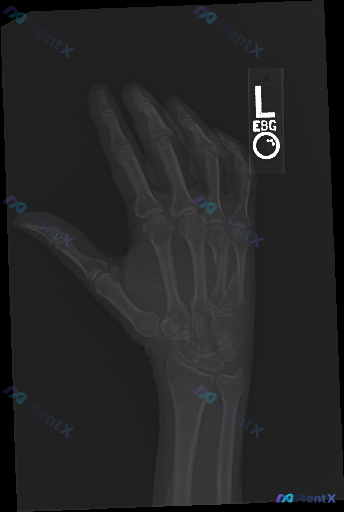

整理到一张左手正位X光片的术后复查资料,标注“L”,覆盖掌骨、近端指骨及部分腕关节。 先把看到的几个点列出来: 1. 第3掌骨有钢板+多枚螺钉固定,形态和骨干弧度基本匹配 2. 第3掌骨干能看到透亮线 3. 透亮线附近有模糊的骨痂影 4. 周围软组织没看到明显肿胀,也没肿块或钙化 5. 掌指、指间关...